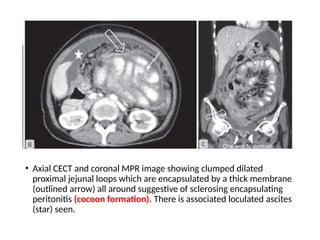

• Axial CECT and coronal MPR image showing clumped dilated

proximal jejunal loops which are encapsulated by a thick membrane

(outlined arrow) all around suggestive of sclerosing encapsulating

peritonitis (cocoon formation). There is associated loculated ascites

(star) seen.

• Axial CECTand coronal MPR image showing clumped dilated proximal jejunal loops which are encapsulated by a thick membrane (outlined arrow) all around suggestive of sclerosing encapsulating peritonitis (cocoon formation). There is associated loculated ascites (star) seen.